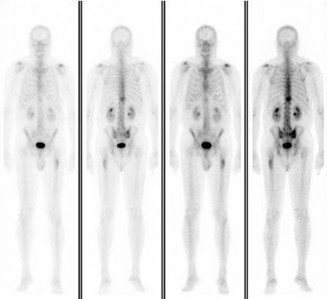

A 15-year-old male presents with deep knee pain awakening him at night. Radiographs show a permeative destructive lesion in the distal femoral metaphysis with a 'sunburst' periosteal reaction and Codman's triangle.

Biopsy confirms high-grade conventional osteosarcoma. What is the most critical prognostic factor for long-term overall survival in this patient?

Explanation

For localized high-grade osteosarcoma, the most important prognostic indicator is the histologic response to neoadjuvant chemotherapy. This is evaluated during the definitive resection. A 'good response' is typically defined as greater than 90% or 99% tumor necrosis. Patients who achieve this level of necrosis have a significantly improved disease-free and overall survival rate compared to 'poor responders' who have extensive viable tumor cells remaining.